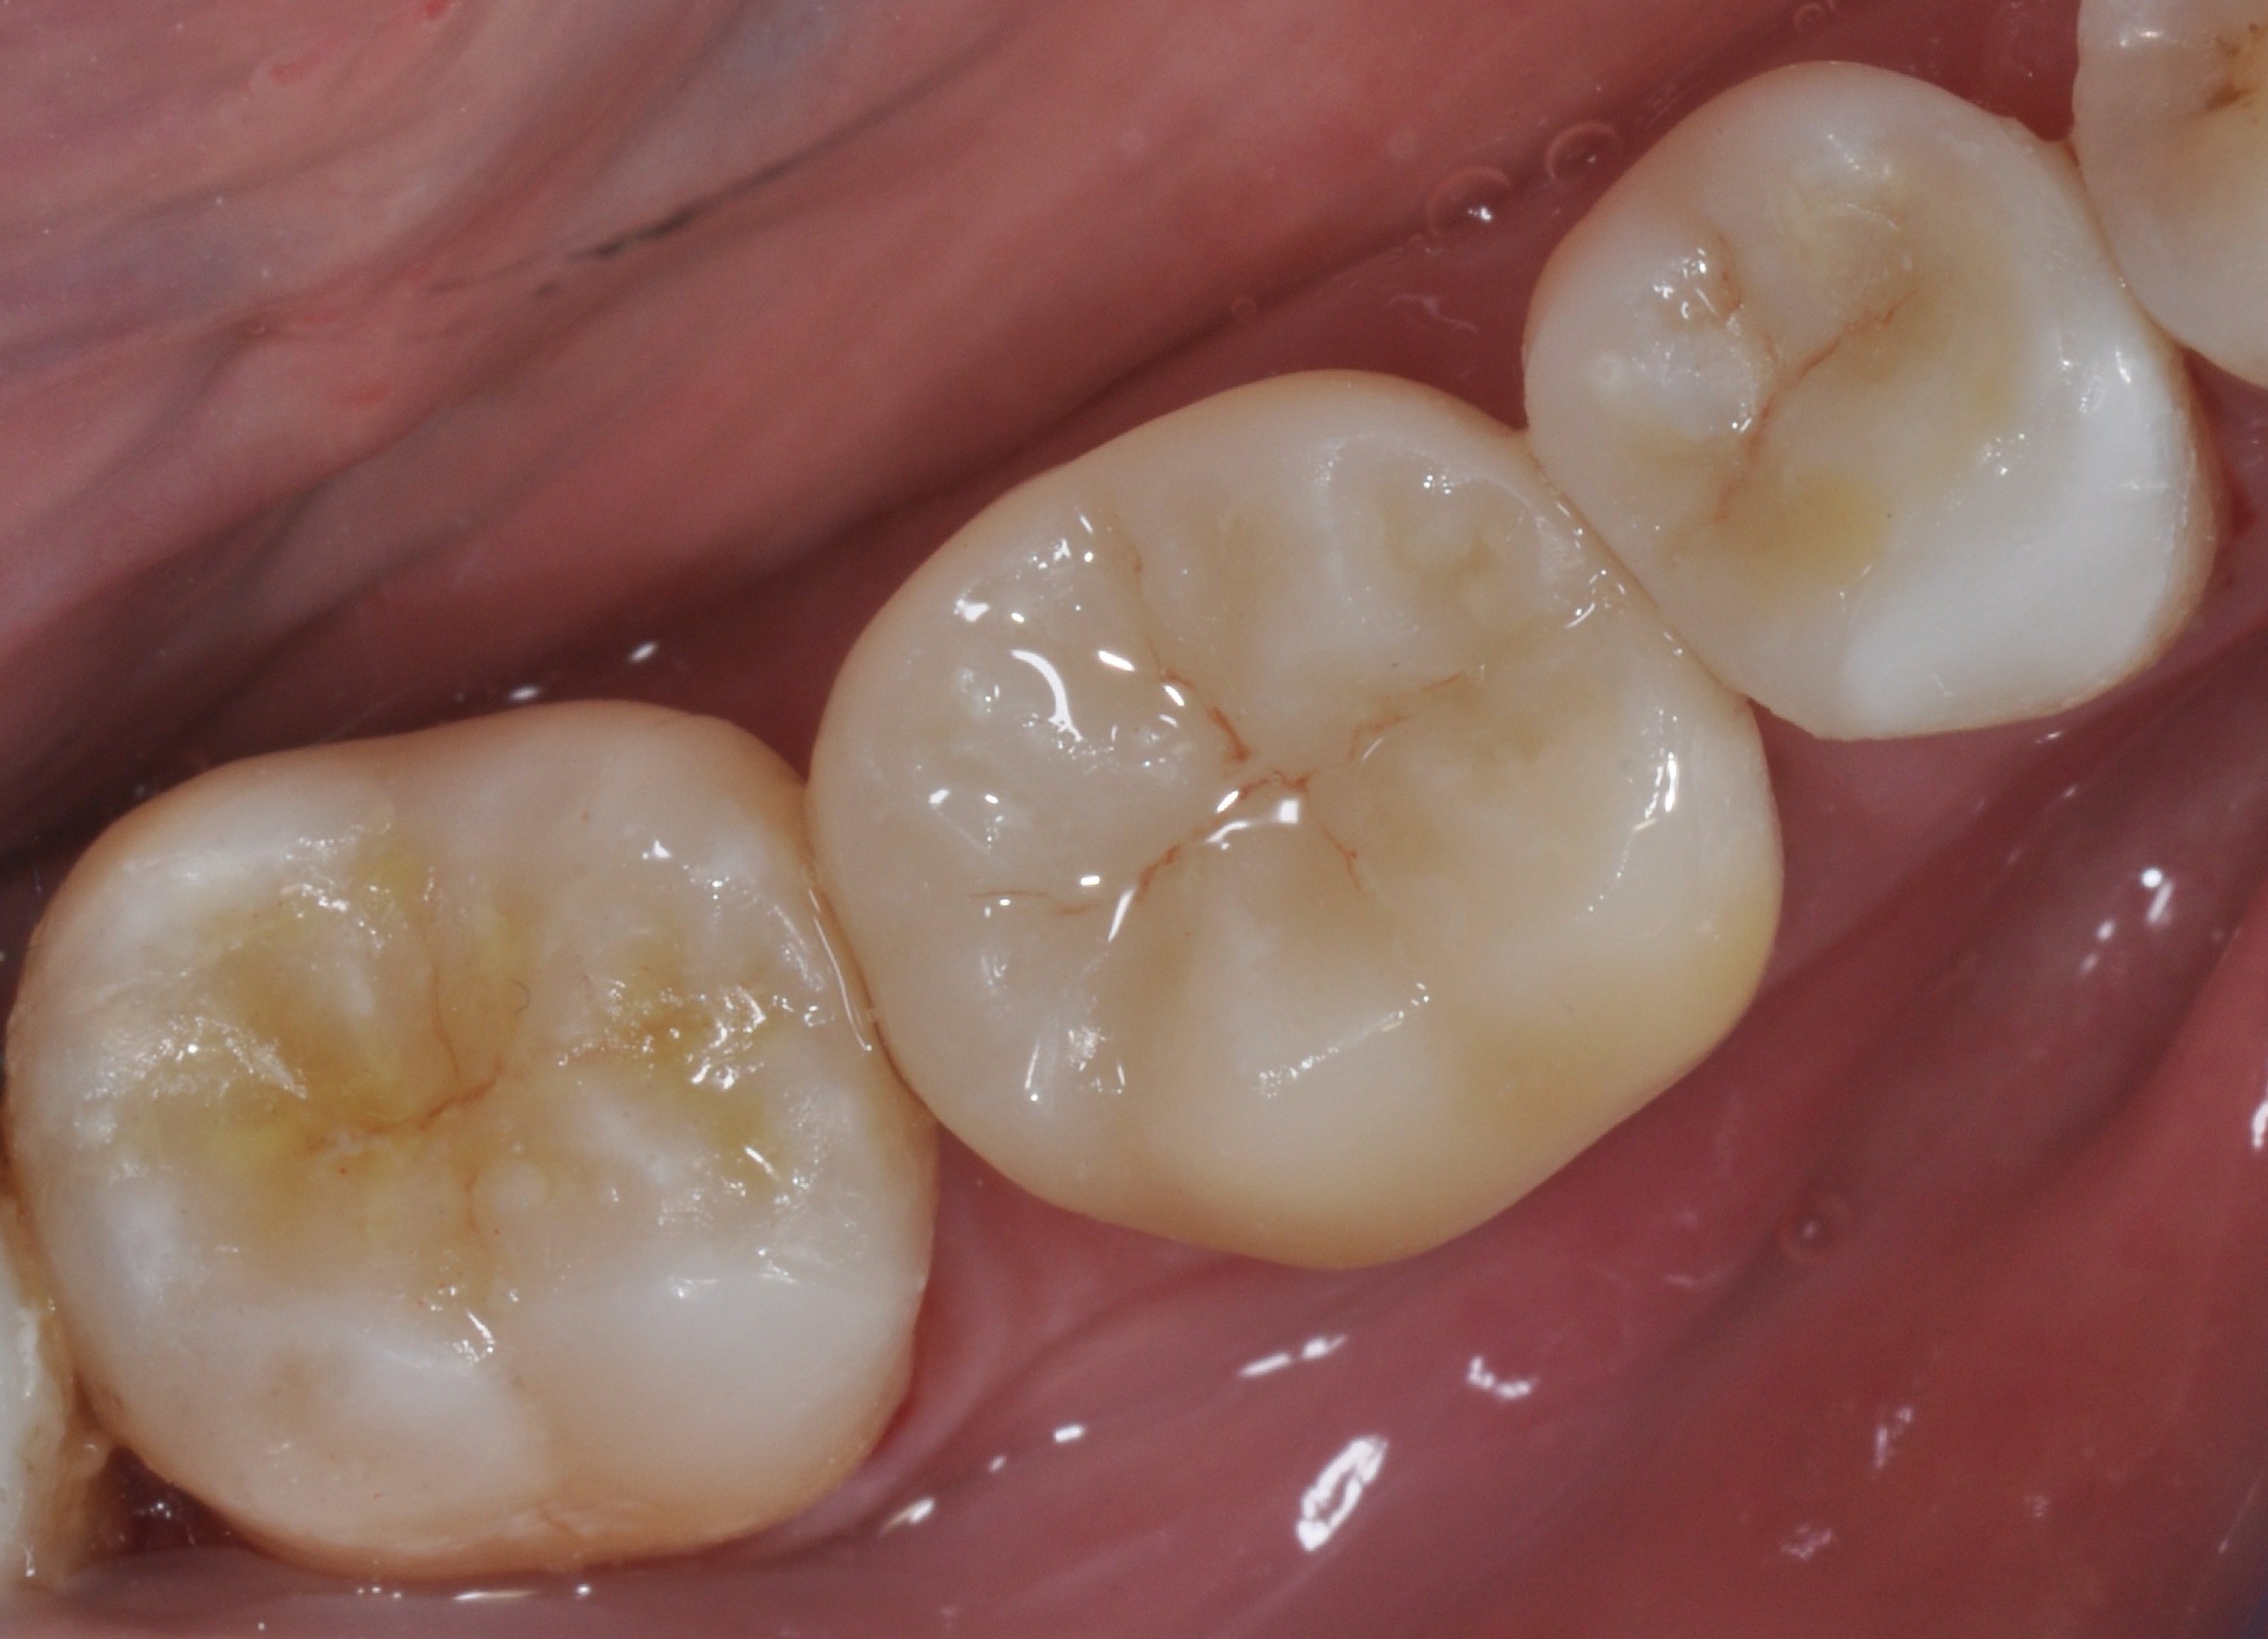

Dopo

Sostituzioni delle otturazioni in amalgama con Intarsi in ceramica.